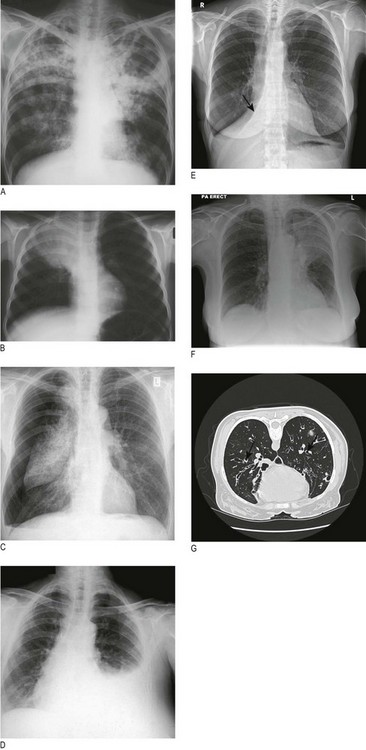

Hypertrophic pulmonary osteoarthropathy is rare and almost always associated with lung cancer, usually squamous cancer. Pronounced clubbing of fingers and toes occurs, with pain and swelling affecting the wrists and ankles. X-rays of the distal forearm and lower legs show subperiosteal new bone formation separate from the cortex of the long bones (Fig. 7.7).